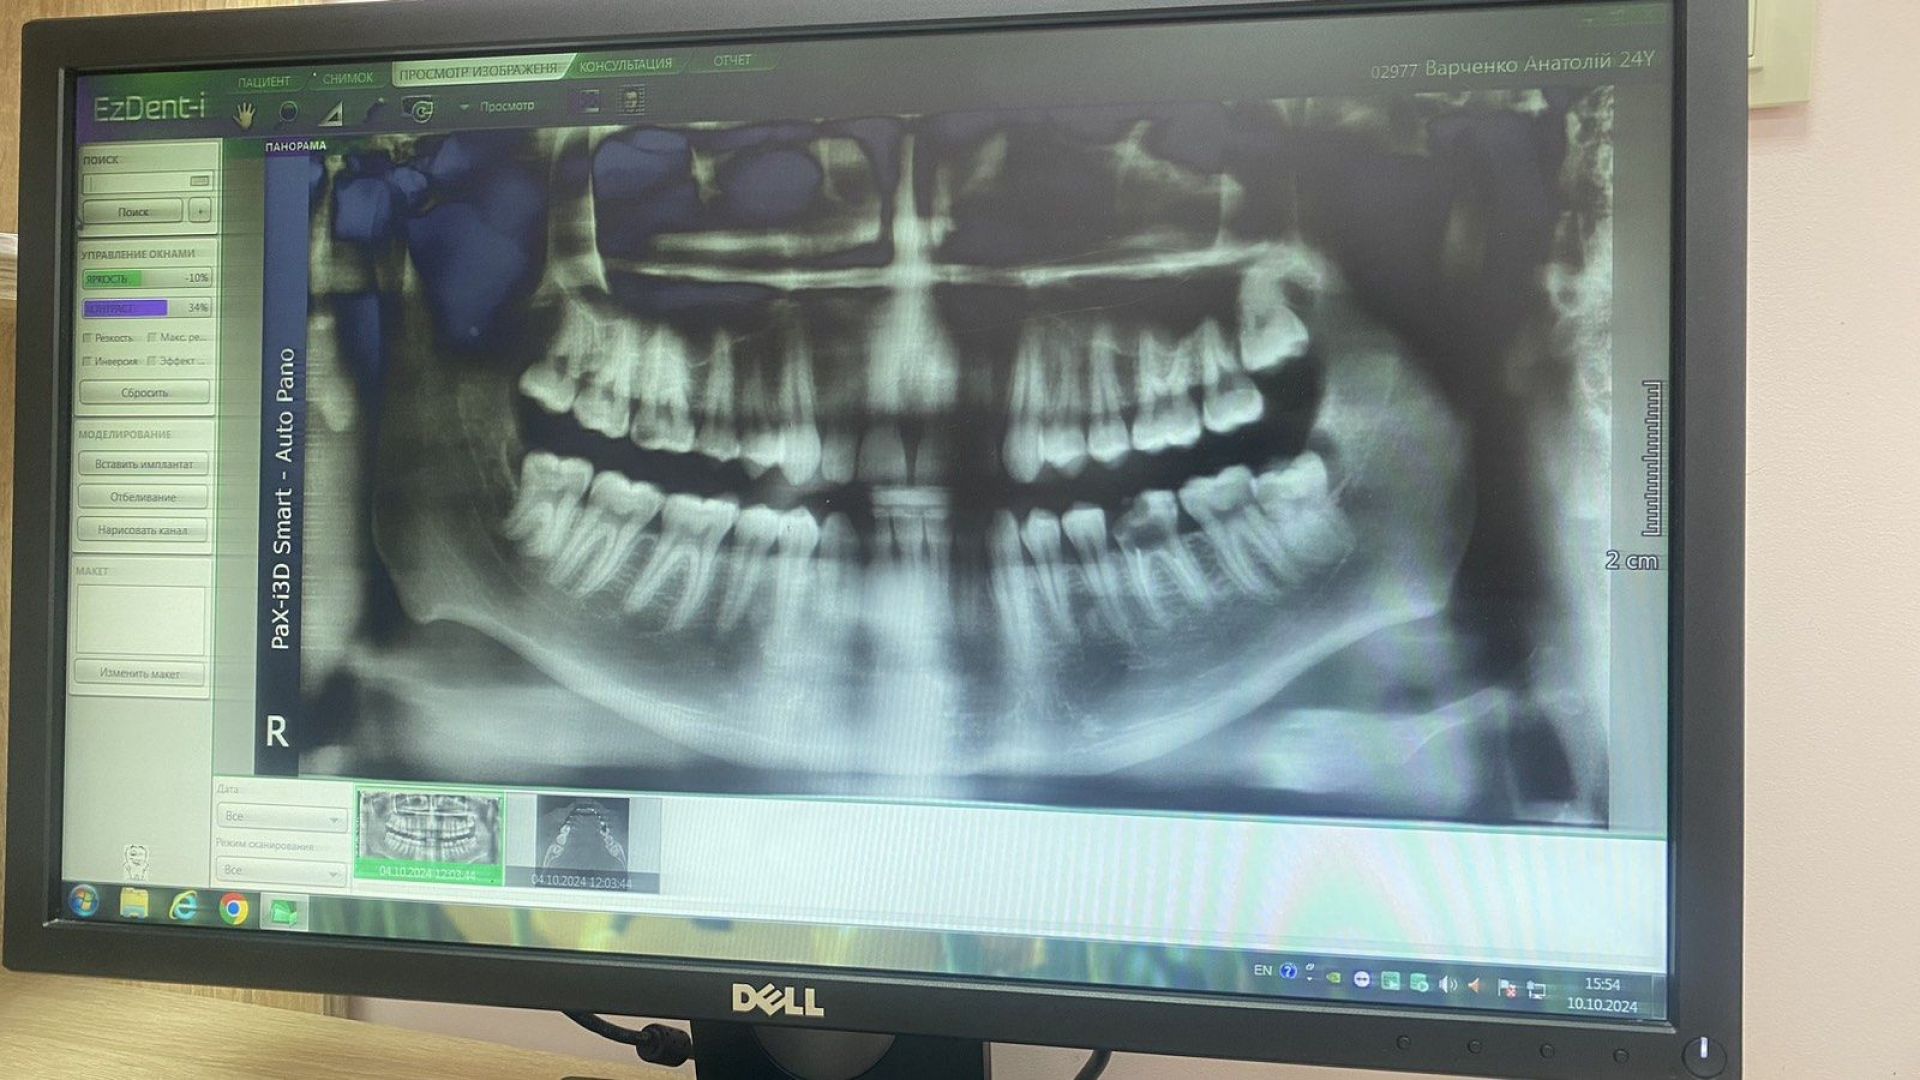

Для точної діагностики стоматологія «Добрий лікар» використовує комп'ютерну томографію (КТ). Завдяки сучасним апаратам знижено променеве навантаження, а процедура триває лише кілька секунд. 3D знімок дозволяє отримати повну інформацію про стан зубів і щелепної системи, що забезпечує індивідуальний підхід до кожного пацієнта.

- Комп’ютерна томографія (КТ) – дає можливість отримати тривимірні зображення зубів і щелеп для детального аналізу стану пацієнта.

- Панорамний знімок – дозволяє побачити загальний стан всієї ротової порожнини та щелепної системи.

- Рентген – швидкий і ефективний спосіб діагностики прихованих проблем, таких як карієс або ураження коренів.

VETUSHINSKYI clinic — це передовий стоматологічний центр у Хмельницькому, який поєднує високий рівень медичних послуг з використанням новітніх технологій. Клініка обладнана сучасним німецьким устаткуванням від лідерів стоматологічного ринку, що дозволяє проводити всі види лікування з максимальною точністю. Зокрема, у VETUSHINSKYI clinic доступна комп'ютерна томографія прямо на місці, що значно покращує діагностику та планування лікування.

Однією з ключових інновацій є застосування томографу Veraview X800, який забезпечує високоякісні 2D та 3D зображення. Завдяки його точності, лікарі можуть краще планувати лікування, а низький рівень опромінення робить процедури безпечними для пацієнтів. Висока роздільна здатність дозволяє бачити найдрібніші деталі, що є особливо корисним для діагностики складних випадків, таких як захворювання зубів та ясен.